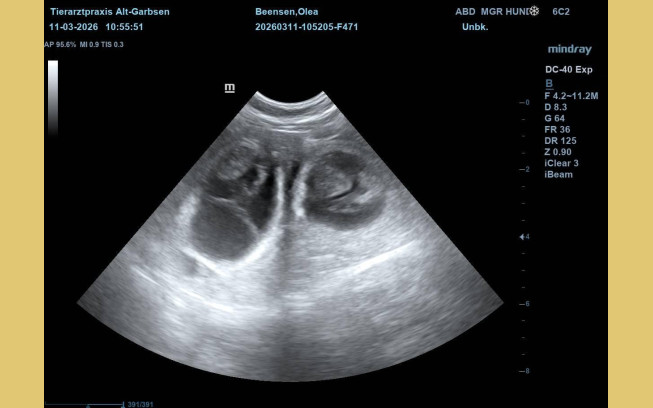

Update vom 11.03.2026:

Heute war ein ganz besonderer Tag. Olea war zum Ultraschall. Schon seit einigen Tagen hatten ihre Besitzer das Gefühl, dass sich etwas verändert hat. Sie war ruhiger und anhänglicher geworden - und ihr Bäuchlein schien sich leicht zu runden.

Beim Ultraschall war es dann eindeutig. Kleine, deutlich erkennbare Welpen. Auf dem Bildschirm waren mehrere winzige Herzschläge zu sehen. Freude, Aufregung und Ehrfurcht - alles zusammen stellte sich bei den Besitzern ein. Olea lag ganz entspannt - als wüsste sie, dass in dem Moment etwas ganz Wundervolles passiert. Jetzt beginnt die spannende Zeit der Vorbereitung. In den nächsten Wochen wird alles für die Ankunft der kleinen "vom Jademeer´chen" vorbereitet. Nicht mehr lange.....